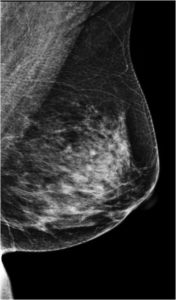

59 Yr old female, referred from outside for suspicious microcalcifications in left breast.